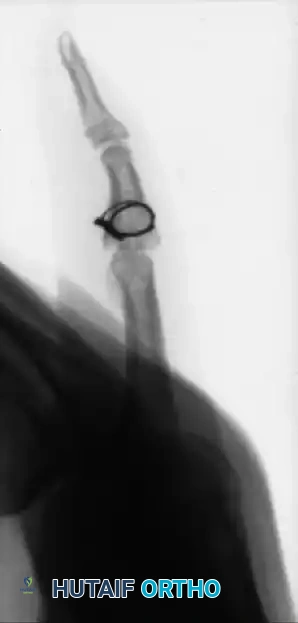

FIGURE 67-75: A, Malunited phalangeal fracture with rotational deformity. B, After treatment by osteotomy through the proximal end of the bone and fixation with two Kirschner wires. Healing is usually more rapid after osteotomy at this metaphyseal level than after one at the old diaphyseal fracture site.